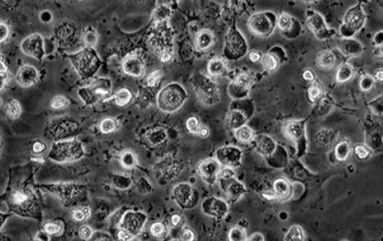

Before-After: Levend Bloed Analyse – Van Rouleaux-Vorming naar Vrije Stroom

Links: Bloed na 10 minuten bellen zonder bescherming – duidelijke klontering (rouleaux), wat zuurstoftransport belemmert en vermoeidheid veroorzaakt. Rechts: Na harmonisatie met MemonizerCOMBI – soepele doorbloeding, optimale zuurstofopname. Wetenschappelijk bewezen: Meer energie, minder ontstekingen.